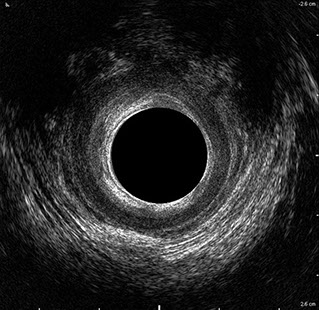

L’ecografia transanale è un esame diagnostico per immagini che consiste nell’introduzione di un trasduttore ad ultrasuoni. Le immagini qualitativamente migliori del canale anale sono ottenute usando un trasduttore rotante, montato in un manipolo rigido, che fornisce un’immagine a 360°. Con le apparecchiature più moderne è anche possibile ottenere immagini tridimensionali.

L’ecografia transanale permette di distinguere la sottomucosa che riveste il canale anale, lo sfintere anale interno, e lo sfintere anale esterno.